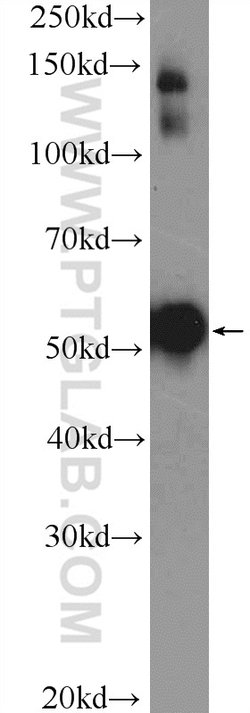

This antibody is specifically against KRT7.

Cytokeratin 7 blocks interferon-dependent interphase and stimulates DNA synthesis in cells. Involved in the translational regulation of the human papillomavirus type 16 E7 mRNA (HPV16 E7).Specifications

| Immunocytochemistry, Immunofluorescence, Immunohistochemistry (Paraffin), Immunoprecipitation, Western Blot | |

| 0.15 mg/mL | |